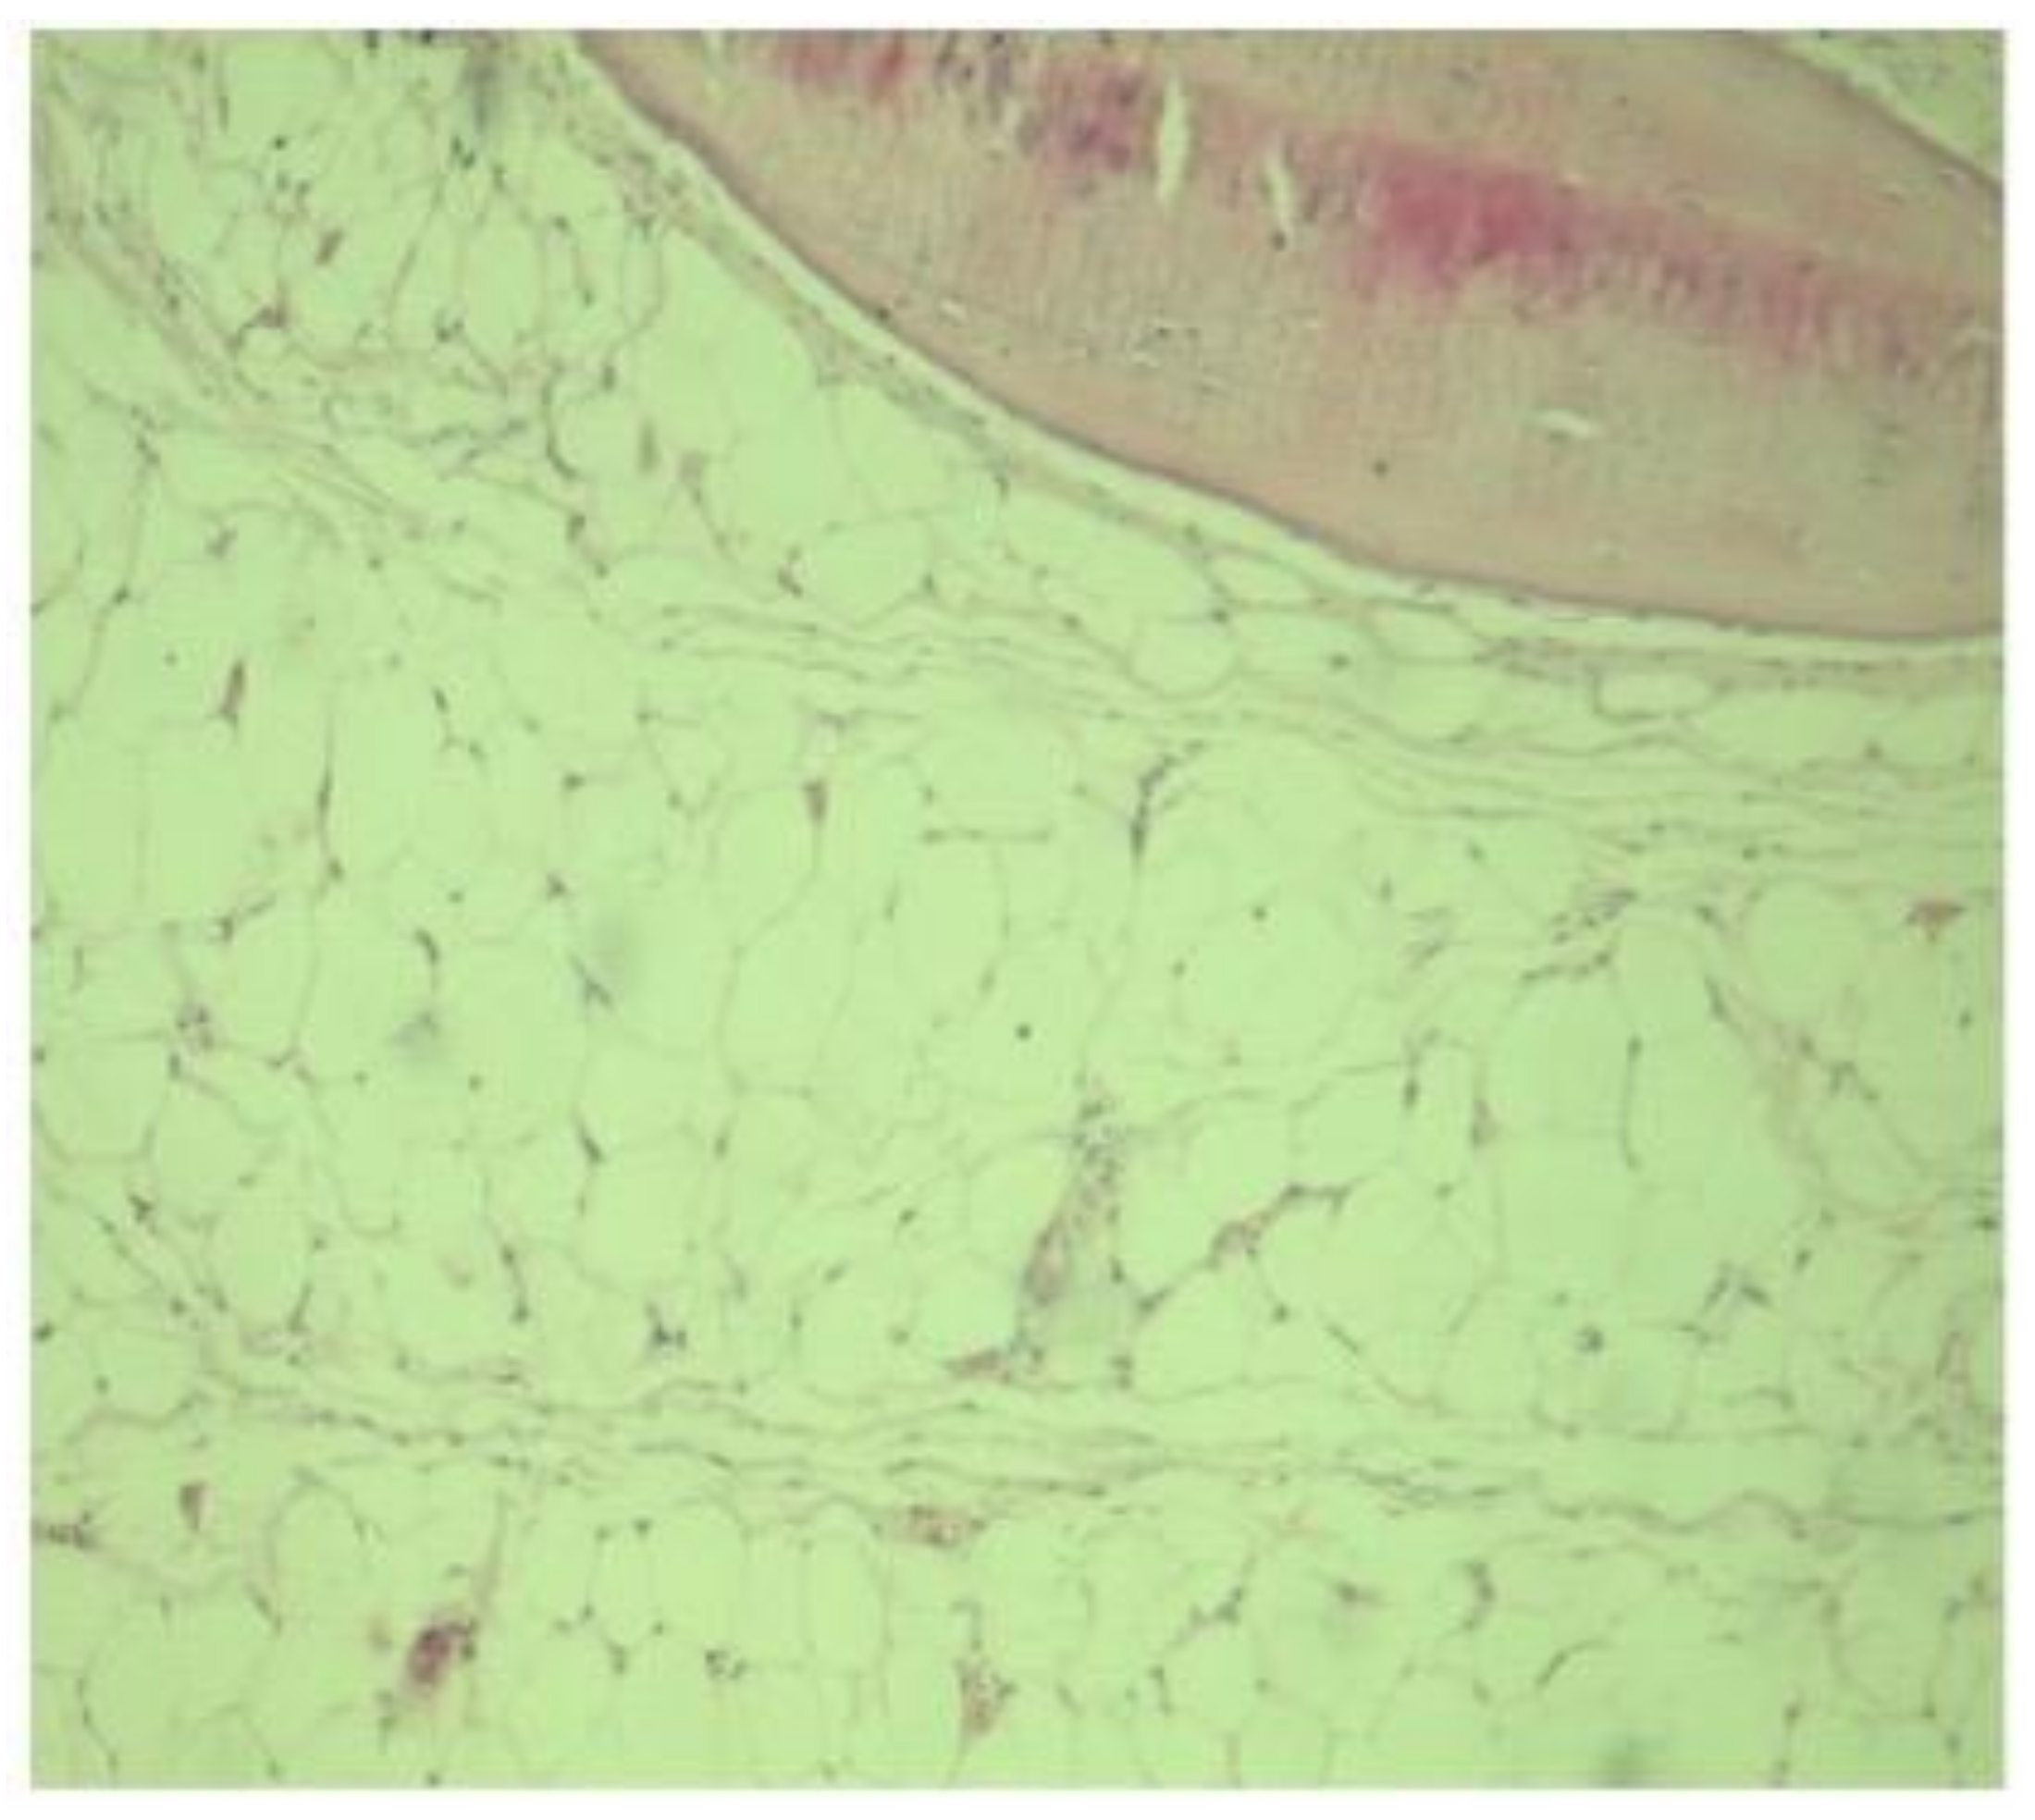

2. Case Presentation